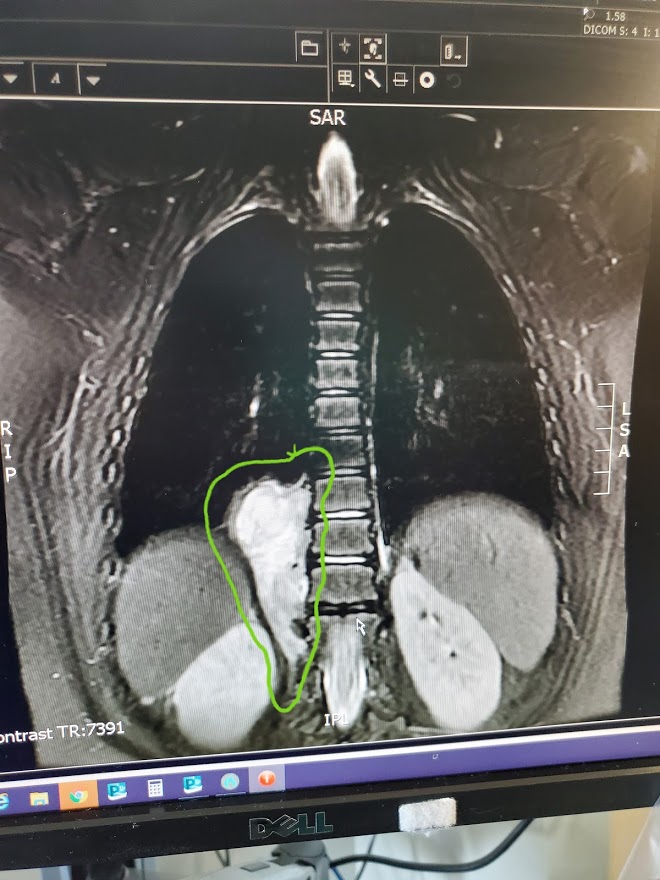

When they entered our room, they were gentle and kind. They were aware of the sensitivity of our aching hearts and they gathered around our sleeping baby girl with such tender kindness. After introductions they confronted the mass, showing us the images of the CT scan we had seen the night before where they had previously suspected an abscess on the Kidney. It was then, in that fragile moment that the doctor pointed to the screen and showed us where the mass was. It was huge. I cried as I studied the image and could see it’s foreign tissue invading her little body, pushing up against her spine, squeezing into un-invited areas. How it was missed, we do not know but what we do know is that there were a lot of little steps, steps we like to call miracles, that led us to where we were right in that moment. The mass was found and now we can move forward in finding out what he is and what he is doing there.

The mass measures 8 x 3.5 x 4cm. It’s ugly and it makes me want to scream. How long has it been growing? What could have caused it? If it is Cancer, why hasn’t she had any other symptoms? Is it hurting her? Where do we go from here?